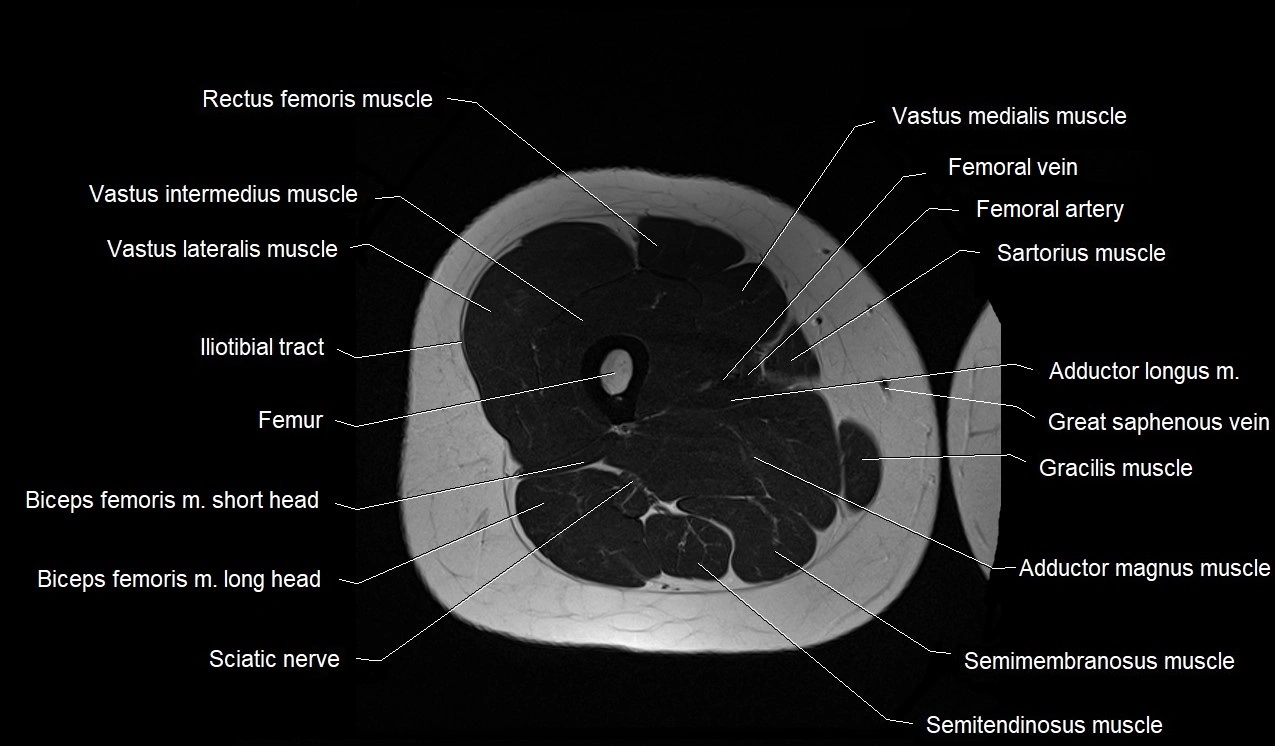

- Biceps femoris muscle (Long head)

- Biceps femoris muscle (Short head)

- Femoral vein

- Femur

- Gracilis muscle

- Iliotibial tract

- Rectus femoris muscle

- Saphenous nerve

- Sartorius muscle

- Semimembranosus muscle

- Semitendinosus muscle

- Tibial nerve

- Vastus intermedius muscle

- Vastus lateralis muscle

- Vastus medialis muscle